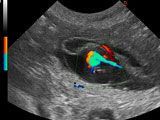

Für die Belegung mit Iusha haben wir uns für den Deckrüden Sämi von der Balmfluh entschieden. Sämi stammt aus interessanten, alten jagdlichen Linien. Iusha hat 2 Hündinnen geworfen.